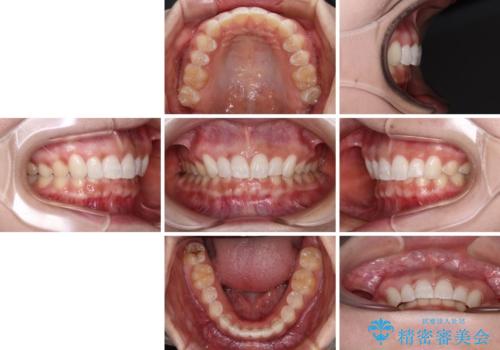

前歯のデコボコを治したい インビザライン矯正治療

- 前歯のデコボコ気になるとのことで来院された患者様です。

下顎骨が上顎骨に対して右側にシフトしており、さらに下顎が後方に位置しているため、非常に強い咬合力で食いしばっている状態でした。

上下顎ともに歯列全体の後方移動とIPR(歯と歯の間を削る)によってデコボコが解消するように設計し、インビザラインにより治療を行うこととしました。

強い咬合力による臼歯部の噛みにくさと、それに伴う歯の移動の鈍さに悩まされ、非常に長い期間を要することとなりました。

上下正中位置は、治療開始時よりは改善したものの、ここが限界であろうというところでのゴールとなりました。

下顎前歯の大半が隠れている状態ですが、左右への歯ぎしりはスムーズに行うことができ、就寝時には後戻り防止も兼ねて、食いしばり対策としてマウスピースの使用を継続するようお願いしております。